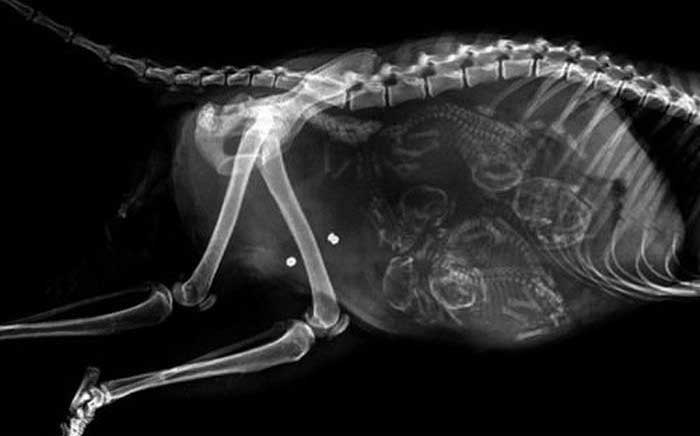

妊娠した様々な動物たちをレントゲン(X線)写真で見てみたギャラリー。サメ、ネズミ、犬、猫など。一度に複数の子供を出産する犬や猫などは特に怖い事に…。

6. ネコ